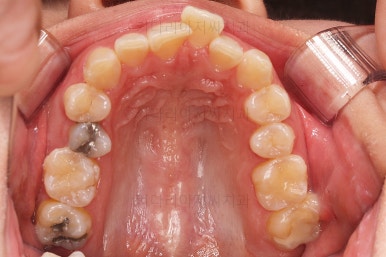

초진 시 입안의 모습입니다.

전반적으로 치열이 삐뚤고, 특정 앞니는 톡 튀어나가 미적으로 좋지 못한 상황이었습니다.

이갈이, 이악물기 습관도 있어서 앞니는 삐뚤어진 채로 치아가 많이 갈려있는 상황이었습니다.